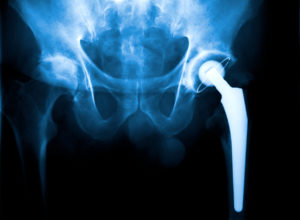

Hip replacement surgery is a common procedure performed in America. This procedure is commonly done on older patients. Hip replacement surgery is executed to alleviate pain and bring back the patient’s mobility and flexibility. There are a variety of reasons why patients may need a hip replacement [Read More]